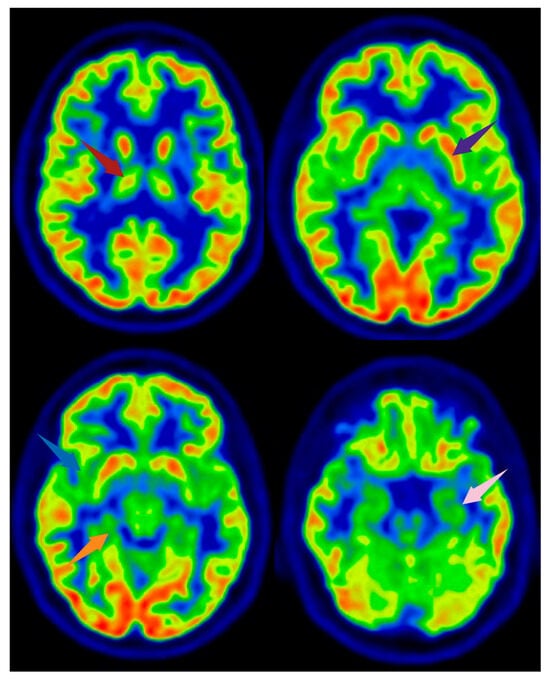

Figure 2. [18F]FDG PET images from a healthy subject. Arrows indicate brain regions commonly reported as altered in FMS, shown here for illustrative purposes. The subject depicted did not have FMS. Axial slices are shown. Red arrow: right thalamus; purple arrow: left lentiform nucleus; blue arrow: right insula; orange arrow: parahippocampal gyrus; pink arrow: medial temporal cortex. Image created using BioRender.com.

Several PET studies have investigated alterations in regional cerebral glucose metabolism in FMS patients using [18F]FDG. Most of the findings have been controversial, as they have failed to demonstrate any statistically significant difference in brain glucose metabolism between treatment-naïve FMS patients and healthy subjects [25,26] (Figure 2 and Figure 3).

The comparison of FMS patients with good and poor responses to medical pain reduction treatment revealed that different brain structures are involved in pain modulation in [18F]FDG PET studies [25,26]. It was found that poor responders show significantly greater metabolism in the left thalamus, bilateral lentiform nucleus, and right parahippocampal gyrus than good responders [27]. This is particularly interesting because an earlier study found that the same brain regions were involved in the analgesic effects of electroconvulsive therapy for FMS-related pain [28]. This effect has been linked to altered thalamic activity following transcranial direct current stimulation and complex changes in gray matter volume [29,30].

[18F]FDG PET scans have also revealed that the insular metabolic hypoactivity is associated with the development of hyperalgesia [31]. Peyron et al. have pointed out that the insular cortex as one of the regions most consistently activated by noxious stimuli related to intensity coding [32]. The insula is also a critical point in the interconnection of dopaminergic (DAergic) and gamma-aminobutyric acid (GABA) activity because GABAergic interneurons are involved in its DAergic modulation [33]. GABA greatly inhibits neuronal activity within the insula; thus, a reduction in insular GABAergic neurotransmission lowers the pain threshold and leads to the hyperalgesia observed in chronic pain conditions [27,34,35,36].

Presynaptic DA transporters (DATs), which remove DA from the synaptic cleft after phasic activation, also seem to play a role in pain modulation. Furthermore, one [18F]DOPA PET study has found that DA metabolism is significantly lower in FMS patients than in controls not only in pain cortex regions such as the brainstem, thalamus, and multiple areas of the limbic system, but also in the ventral tegmental area (VTA) [38] (Figure 2).